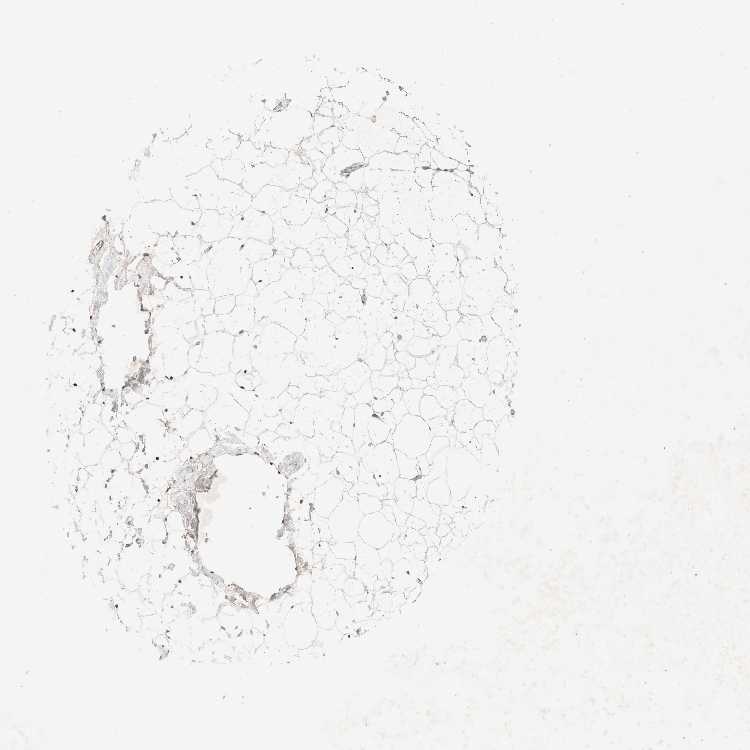

SOFT TISSUE 2 - Antibody stainingi

Antibody staining in the annotated cell types in the current human tissue is reported as not detected, low, medium, or high, based on conventional immunohistochemistry profiling in selected tissues. This score is based on the combination of the staining intensity and fraction of stained cells.

Each image is clickable and will lead to virtual microscopy that enables deeper exploration of all samples and also displays staining intensity scores, fraction scores and subcellular localization as well as patient and tissue information for each sample.

Antibody HPA024659

Fibroblasts Not detected

Peripheral nerve Medium